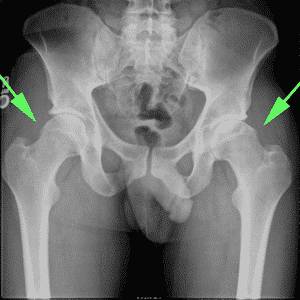

Норма

Когда появляются ядра окостенения? Тазобедренные суставы формируются на восьмом месяце беременности. Норма ядер окостенения тазобедренных суставов у новорожденных — 3-6 мм.

Сустав не похож по своему строению на взрослый:

- он имеет уплощенную суставную впадину, расположенную вертикально;

- связки сустава очень эластичные;

- головка бедра удерживается в суставной впадине напряжением суставной капсулы при помощи круглой тазобедренной связки;

- хрящевая пластинка вертлужной впадины не дает сместиться вверх бедренной кости.